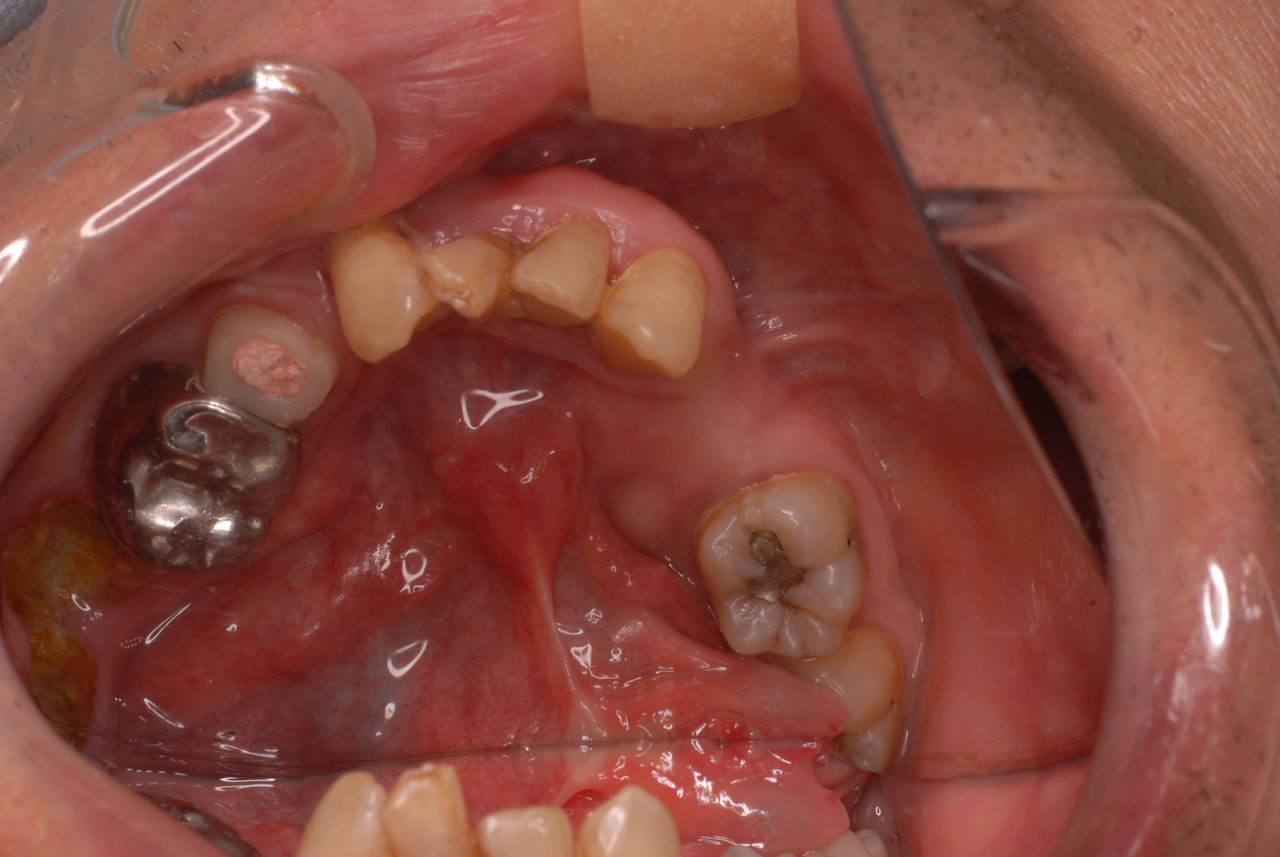

親知らずを取ることを嫌がる方が多いのですが、もし親知らずとその隣の14歳大臼歯の間に虫歯ができたり歯周病を罹患した場合、どれほど治療が大変で再発も起こりやすいか理解できない方がおおいのです。

写真左下の親知らずが痛くなり抜歯しました。その後歯茎を除去して虫歯を露出させる処置を二回ほどしています。

レントゲンでは小さいですが、こう言う虫歯が一番怖いのです。

治療の成功率は極めて悪くすぐ再発しやすいのです。